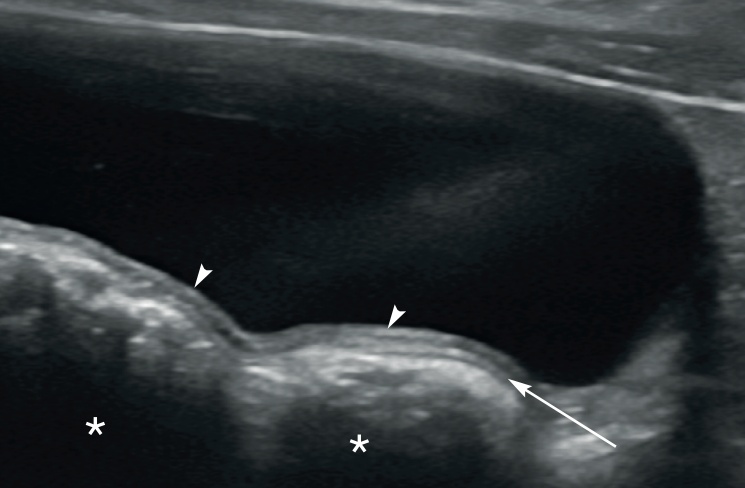

방광의 파열을 알아내기 위해서는 초음파 검사보다 양성 조영제를 이용한 역행성 방광조영술(retrograde cystography)이 더 좋습니다. 굴절 허상(가장자리 음영)으로 에코 소실이 발생해 곡선형의 방광벽 일부가 불연속으로 보이는 현상이 나타나는데, 특히 복강 내 유리 복수가(free peritoneal fluid) 있는 경우 두드러집니다(그림 14).

방광요막관 게실은 고양이에서 드물게 관찰되며, 무증상일 수도 있지만 재발성 세균성 요도 감염을 유발할 수 있습니다. 이는 방광 정점에 위치한 요막관이 제대로 닫히지 않아 발생하는 선천적 기형입니다. 초음파 검사에서 방광 내강이 볼록하게 돌출되어 비정상적으로 뾰족한 모양을 보이거나 방광벽 내에 국소적인 함몰로 나타납니다. 가장 흔하게는 방광의 두 개복측(정점)에서 발견됩니다.

이 고양이는 생후 4개월에 혈뇨, 배뇨곤란, 부적절한 배뇨 증상으로 처음 내원하여 요로감염으로 치료받았습니다. 이후 2개월 뒤 비슷한 임상 증상으로 다시 내원했습니다. 복부 초음파 검사 결과, 방광의 머리 쪽 부위에 2.2 x 2.2 x 1.4 cm 크기의 다층 종괴가 발견되었습니다. 특이하게도, 방광의 머리 쪽 꼭대기 부분이 뭉툭해지고 중앙부가 함몰되어 있었습니다. 바깥쪽의 고에코성 장막층은 함몰된 지점에서 아래쪽으로 종괴의 중심부까지 이어져 있었습니다(그림 17, 18). 컬러 도플러 초음파를 사용하여 종괴 내 혈류가 있음을 확인했습니다. 무에코성 소변이 종괴 바로 아래쪽 방광 내강에서 관찰되었습니다. 초음파 소견을 바탕으로 방광 내번증으로 추정 진단이 내려졌고, 이후 방광 절개술을 통해 확진되었습니다. 내번된 조직을 제거하기 위한 부분 방광 절제술과 동반된 요로감염에 대한 항생제 치료 후 모든 임상 증상이 호전되었습니다.